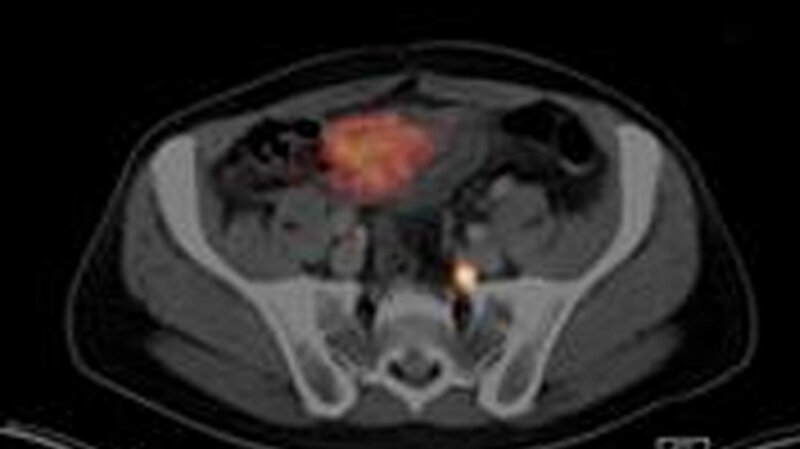

Mit Hilfe einer Positronen-Emissions-Tomographie (PET) die mit einer CT oder MRT kombiniert wird, lassen sich die nun Strahlung aussendenden Metastasen sichtbar machen und zeitgleich die genaue Lage der markierten Zellen bestimmen. Bei der Entwicklung und Anwendung des Verfahrens arbeiten Radiochemiker, Nuklearmediziner und Urologen der TUM eng zusammen. Anhand der gewonnenen Daten können die Ärzte erkennen, ob eine Operation sinnvoll wäre und gemeinsam mit dem Patienten die Entscheidung für oder gegen einen Eingriff treffen. Neben den Ergebnissen der PET/CT-Untersuchung fließen aber auch Faktoren wie die physische Verfassung des Patienten in die Empfehlung der Mediziner ein.

Durch an der TUM entwickelten Radioliganden können auch sehr kleine Metastasen sichtbar gemacht werden. Nuklearmedizin / TUM)